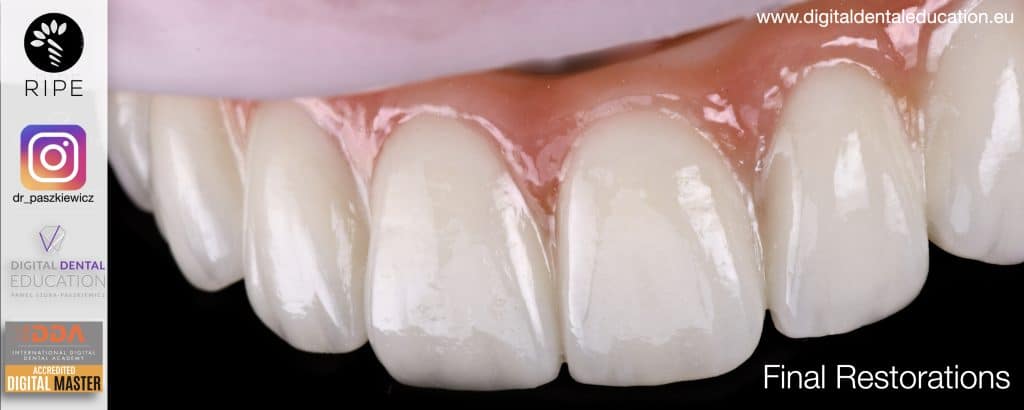

He has invented an AllonX non-impression protocol leading to final restorations post immediate implant full-arch loading, incorporated with desktop scanner (MEDIT) and ModJaw capturing of natural patient’s functional and mastication movements.